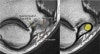

연속적인 관상면 영상에서 UCL을 볼 수 있습니다.

정상적인 UCL이 sublime tubercle에 확실하게 붙어 있는 것을 볼 수 있습니다.

Proximal part에서 약간의 high signal이 보이는 것은 정상입니다(arrow).